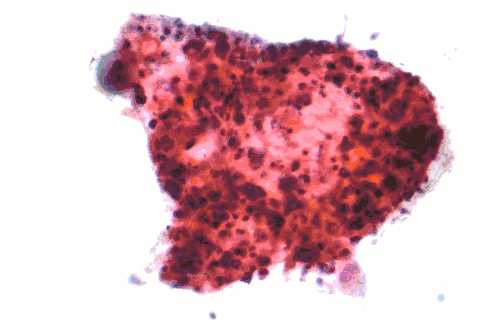

Squamous-cell lung carcinoma

Squamous-cell carcinoma (SCC) of the lung is more common in men than in women. It is closely correlated with a history of tobacco smoking, more so than most other types of lung cancer. According to the Nurses' Health Study, the relative risk of SCC is around 5.5, both among those with a previous duration of smoking of 1 to 20 years, and those with 20 to 30 years, compared to "never smokers" (lifelong nonsmokers).[14] The relative risk increases to about 16 with a previous smoking duration of 30 to 40 years, and roughly 22 with more than 40 years.[14]

Micrograph of a squamous carcinoma, a type of nonsmall-cell lung carcinoma, FNA specimen, Pap stain. -